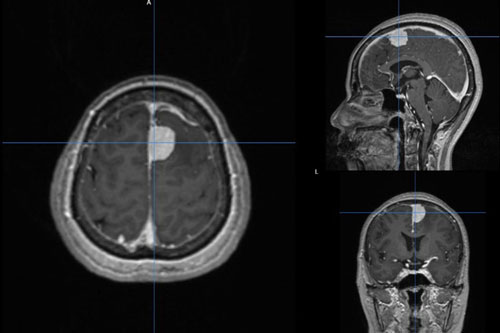

Các bác sĩ Khoa Ngoại Thần kinh, Bệnh viện quận Thủ Đức (TP.HCM) vừa phẫu thuật thành công khối u màng não cho nữ bệnh nhân 58 tuổi.